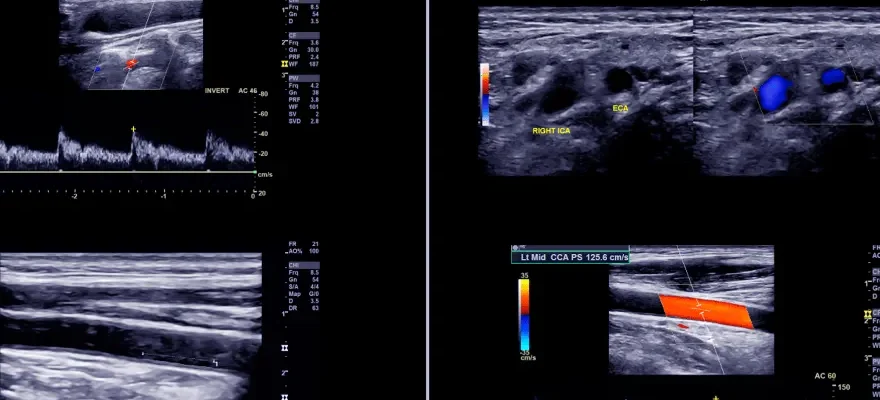

Portal ven renkli Doppler ultrasonu işlemi sırasında, hasta genellikle sırtüstü yatar ve karın bölgesi açıkta bırakılır. Ultrason jel, cilt üzerine uygulanır ve ultrason probu (transdüser), karın bölgesi üzerinde dikkatlice hareket ettirilir. Renkli Doppler teknolojisi, kan damarlarındaki kan akışını renkli bir harita olarak görselleştirir. Bu, damarlardaki kan akış hızını ve yönünü belirlemeye ve anormallikleri saptamaya yardımcı olur. İşlem, hastaya herhangi bir rahatsızlık vermez ve genellikle 30 ila 60 dakika arasında sürer. Bu yöntem, portal ven sisteminin ve çevresindeki damarların detaylı bir değerlendirmesini sağlayarak, doktorlara değerli tanısal bilgiler sunar.